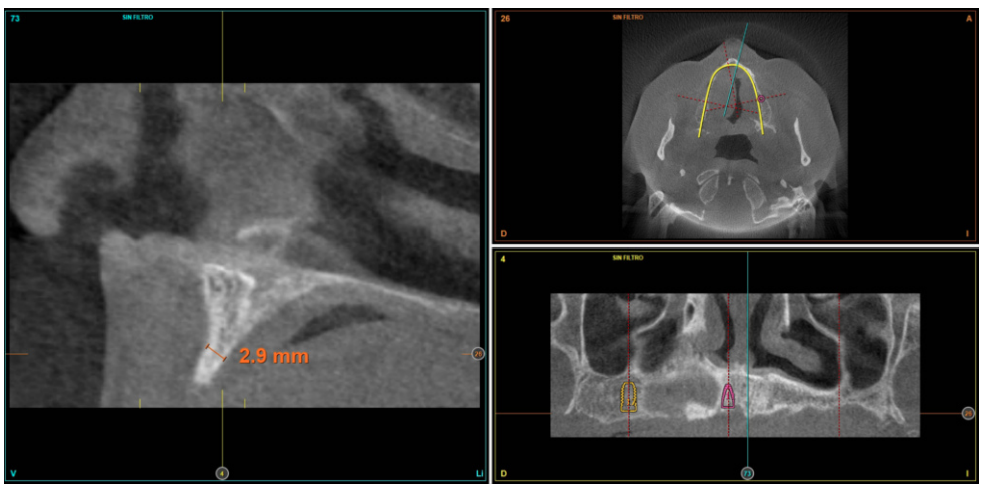

Posteriormente, se procede a la realización de un Cone-beam dental que ofrece una visión más exacta del tipo de rehabilitación implantológica que se pueda plantear. En los cortes correspondientes al maxilar superior, se observan zonas donde puede realizarse la inserción directa de los implantes como las correspondientes a 16 y la zona del incisivo central de este cuadrante (Figuras 4-5) o en el segundo cuadrante el área de 27. En cambio, en la zona correspondiente a los dientes 21 y 23 existe una atrofia horizontal importante, con una anchura ósea residual de aproximadamente 3,5 mm en la zona media de la cresta, con una ampliación en el área más basal de la misma y conservación de ambas corticales. Esto hace que se opte por una técnica de Split de cresta, en este caso en dos fases para poder lograr una mayor anchura final y corregir la inclinación del implante final todo lo posible para lograr una estética en la prótesis final adecuada (Figura 6).

suficiente volumen óseo en anchura y altura para la inserción directa de un implante en esta posición.

En las zonas correspondientes a los dientes 11 y 13 la atrofia horizontal es todavía más marcada. No existe hueso trabecular separando las dos corticales (vestibular y palatina) y la anchura es menor a 2 mm en algunas zonas lo que hace que en esta área se planifiquen injertos en bloque. En la mandíbula se planifican implantes cortos mediante inserción directa, y la zona correspondiente a la rama mandibular será el área donante para los injertos en bloque.

Cuatro meses después de la cirugía inicial de regeneración del maxilar se lleva a cabo un nuevo Cone-beam dental, en el que se planifica la siguiente fase de la cirugía en función de la ganancia ósea que se ha logrado con los injertos en bloque y la técnica de Split en dos fases. En las imágenes podemos observar como en las zonas de máxima atrofia, donde se colocan los bloques se ha logrado una anchura que triplica la inicial (Figuras 19 y 20). En la apertura del colgajo se observa como las imágenes del TAC de planificación se corresponden con la realidad, y además que la zona tratada mediante Split en dos fases ha logrado también una anchura de cresta que ahora permite la retirada de los implantes transicionales y la inserción de nuevos implantes en esta posición, con una mejor situación de partida y eje para la confección posterior de la prótesis (Figuras 21-22). Se procede a la inserción de los implantes y se realiza una prótesis provisional de carga progresiva apoyada en los implantes colocados en la primera fase quirúrgica. De este modo, la paciente puede tener una prótesis fija sobre implantes que servirá para ir dando forma a los provisionales en cuanto a estética y función de cara a la prótesis definitiva (Figuras 23-24).